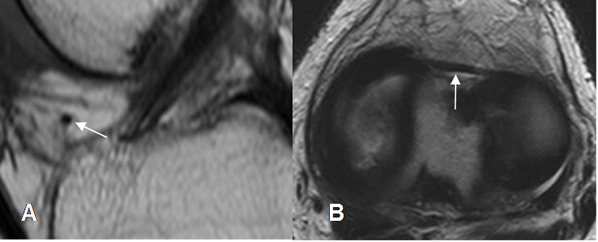

Existen cojinetes grasos en la rodilla, de localización intracapsular y que pueden estar afectados por varias patologías intrínsecas y extrínsecas. Son la grasa suprapatelar o del cuadriceps, la prefemoral y la infrapatelar o de hoffa. (Fig 36).

Fig 36. Cojinetes grasos normales.

A: RM sagital en T1 y B: RM sagital en STIR. Cojinetes normales hiperintensos en T1 y que suprimen en STIR. Grasa suprapatelar (Flecha delgada), grasa prefemoral (Flecha gruesa) y grasa de hoffa. (Punta de flecha).